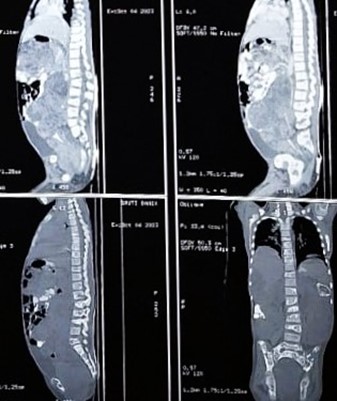

Figure 5: CECT whole abdomen (sagittal view), Postoperative (after few months of defaulter) showing huge intraabdominal SOL almost occupying whole abdomen along with multiple vertebral metastases

Then she again presented with huge abdominal distension and was unable to walk. She was again evaluated for the disease status. The Blood parameters, as on 01/08/2023, were: BetaHCG -> 96120 mIU/ml, CA-125 –> 207.5 U/ml, Sr LDH -> 4180 U/L, AFP –> more than 1000 ng/ml. CECT scan Thorax and Abdomen on 07.08.2023 showed, Large heterogenous enhancing SOL of 8.1 x 6.3 x 6.1 CM in POD, invading and incaving the ano-rectum region with bilateral pleural effusion.